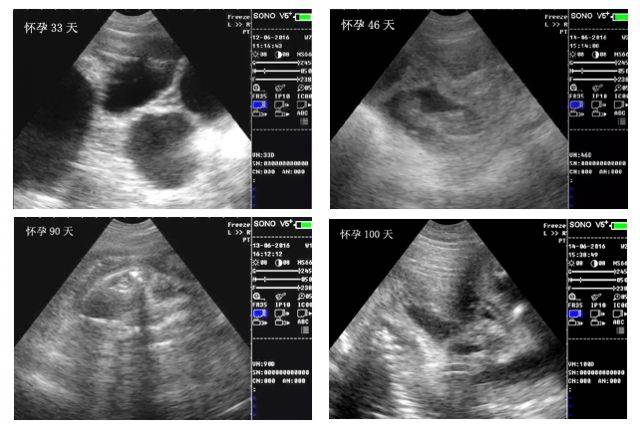

空怀,假孕一看就知道!